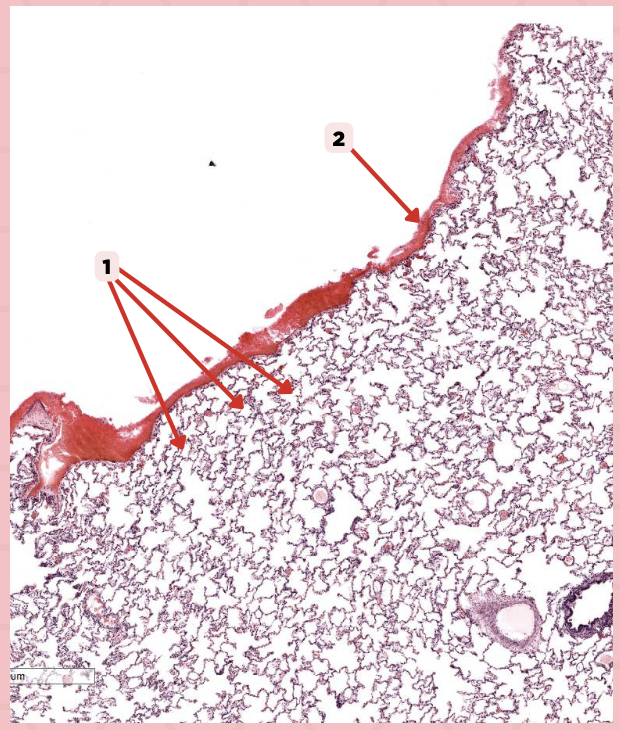

Visceral pleura

Identify the structure labeled as 1.

Alveoli

Identify the structure labeled as 2.

Lumens and Interalveolar septa

Name the irregular spaces and the fine threads of tissue that separate them.

What type of pleura is a thin layer of connective tissues that borders on the outside by mesothelium?

Simple Squamous Epithelium

What epithelium lines the red arrow?